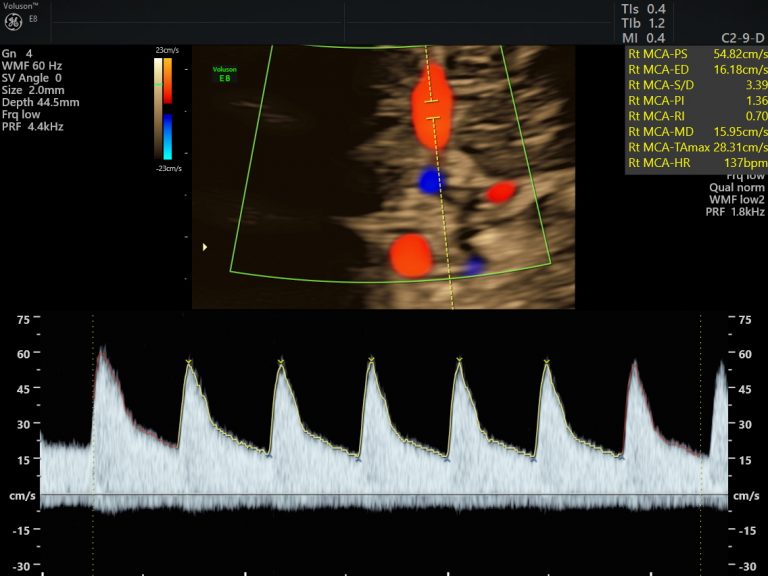

Small for gestational age babies are identified by obstetricians and referred to us for Growth and Doppler studies. This means we evaluated the adequacy of blood flow between the mom and placenta, baby and placenta as well as the flow into the baby’s brain. This information helps to plan the surveillance and delivery plan for the smaller baby meticulously. One always need to measure up the risk of being small intra-uterine, versus the risk of neonatal complications due to preterm delivery.